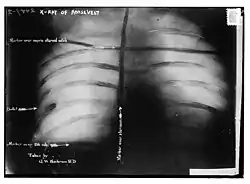

Posteriormente, las sondas y una radiografía mostraron que la bala se había alojado en el músculo del pecho de Roosevelt, pero no había penetrado la pleura. Como los médicos concluyeron que sería menos peligroso dejarla allí que intentar extraerla, Roosevelt llevó la bala consigo por el resto de su vida.

Posteriormente, las sondas y una radiografía mostraron que la bala se había alojado en el músculo del pecho de Roosevelt, pero no había penetrado la pleura. Los médicos concluyeron que sería menos peligroso dejarla en su lugar que intentar quitarla, probablemente recordando lo que le había sucedido al predecesor inmediato de Roosevelt William McKinley, quien murió después de que la herida de la bala se infectara, y Roosevelt llevó la bala consigo por el resto de su vida.[16][17] Años después, cuando le preguntaron por la bala que llevaba dentro, Roosevelt dijo: «No me importa más que si estuviera en el bolsillo de mi chaleco».[18]